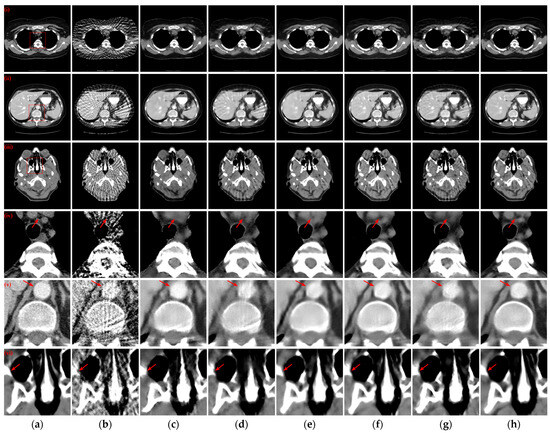

3.5. Ablation Study